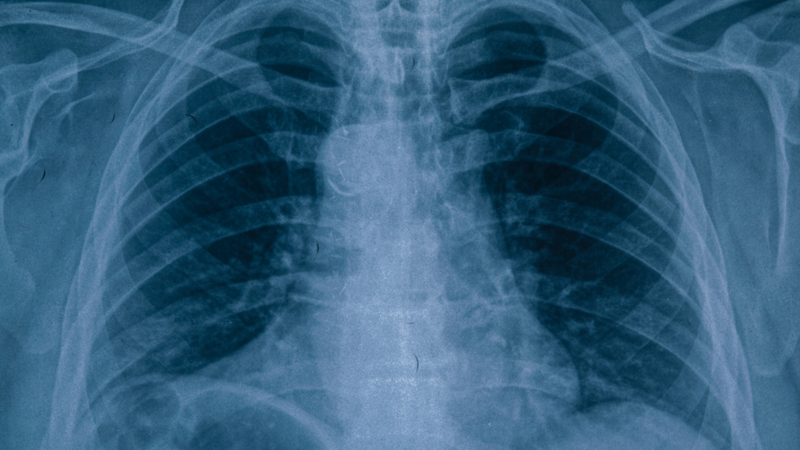

Khi chuyển sang viêm phế quản mạn tính, phim X-quang sẽ có những dấu hiệu đặc trưng hơn cần được lưu ý. Một số hình ảnh phổ biến gồm có tăng đậm vân phổi, do sự tăng tiết dịch nhầy làm dày đặc các vân phổi. Thêm vào đó, thành phế quản thường dày lên rõ rệt, phản ánh tình trạng viêm kéo dài và tổn thương mãn tính. Ở những bệnh nhân mắc kèm bệnh phổi tắc nghẽn mạn tính, có thể quan sát thấy dấu hiệu khí phế thũng như phổi tăng sáng, giảm mạch máu ngoại vi và cơ hoành dẹt do phổi căng giãn quá mức. Đặc biệt, trong trường hợp bệnh tim phổi mạn tính (tâm phế mạn), bóng tim trên phim X-quang có thể to bất thường, thường là do giãn thất phải, kèm theo các dấu hiệu sung huyết phổi hoặc tràn dịch màng phổi.

Ngoài ra, X-quang cũng giúp phân biệt các mức độ tổn thương của viêm phế quản. Với viêm phế quản đơn thuần, phim có thể bình thường hoặc chỉ thấy tăng đậm vân phổi và dày thành phế quản. Khi bệnh tiến triển thành viêm phế quản phổi, trên phim xuất hiện các nốt mờ nhỏ rải rác ở hai bên phổi, đôi khi có tổn thương nhu mô dạng lưới do viêm lan rộng. Trường hợp nặng hơn là viêm phổi thùy, với vùng mờ đặc khu trú theo phân thùy hoặc toàn bộ thùy phổi.